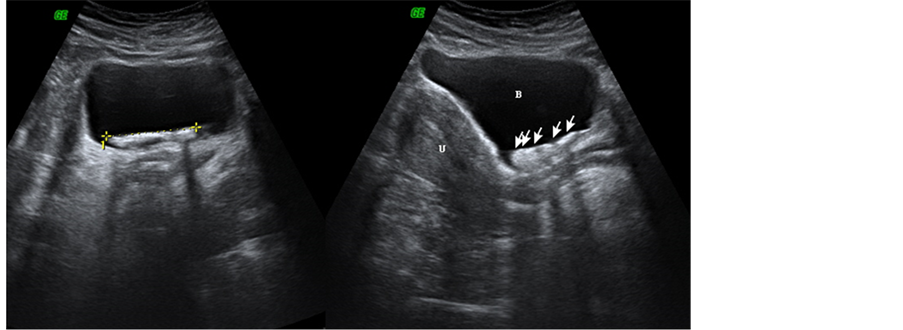

Then the patient was referred to our hospital for further evaluation. Initially a plain abdominopelvic radiography was performed for the patient and calcification of the IUD string and the IUD itself was visible in the pelvic region (Figure 1). Then transabdominal sonography of the pelvis was performed using an ultrasound scanner (GE, USA) equipped with a 3.5-MHz phased-array transducer. The sonographic images revealed a dense intra bladder stone like structure with metallic artifact consistent with a calculus IUD (Figure 2). Also, three dimensional ultrasound imaging showed intra bladder IUD and its calcified components (Figure 3).

Figure 2. Axial and sagittal trans abdominal ultrasound images shows dense intra bladder stone like lesion with metallic artifact (arrows), (U) uterus, (B) bladder.